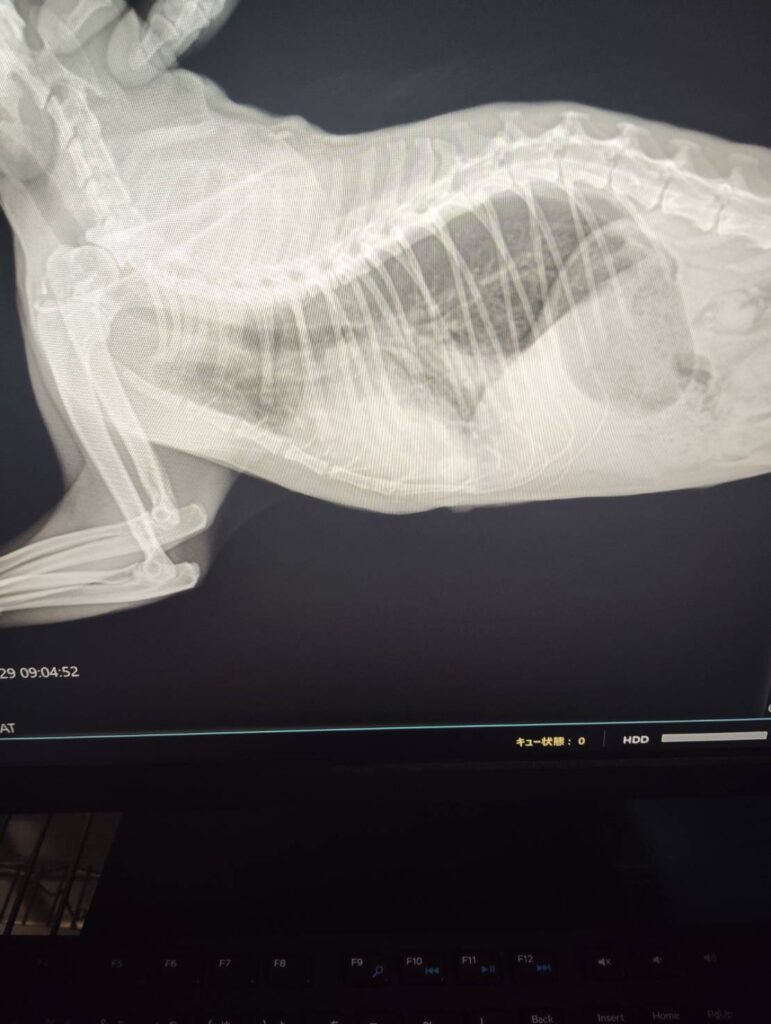

症例 猫 12歳 オス 来院理由 呼吸が早い、食欲がない 身体所見 呼吸回数96回 検査 【血液検査】 ・異常なし 【レントゲン検査】 ・心臓の輪郭不鮮明、心拡大 【心臓エコー検査】 ・左房拡大あり LAAO=1.8 ・心筋中隔壁 6mm 心筋自由壁8mm 診断 肥大型心筋症、肺水腫 方針 入院下で治療開始 3日後、状態良化のため、退院、内服開始し、定期検診の予定 実績に戻る 関連の症例を見る 循環器科 🫀犬の僧帽弁閉鎖不全症(心臓病)と肺水腫について